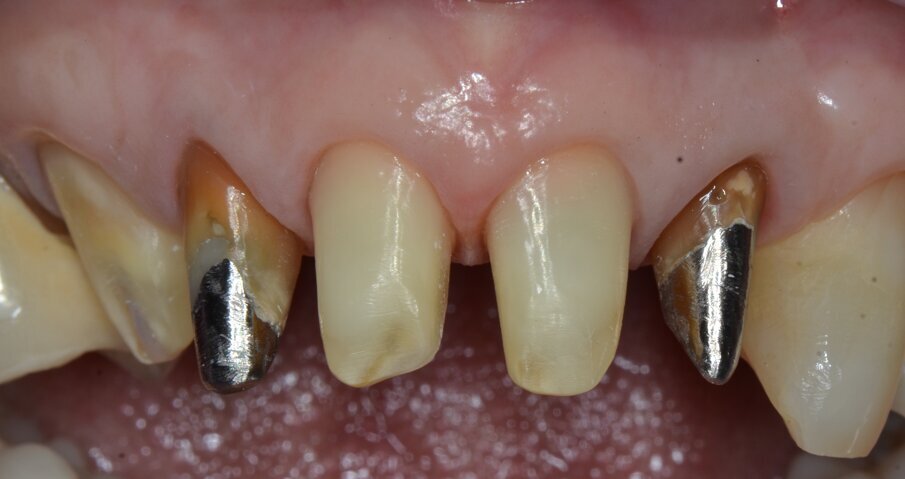

Riguardo al comparto intraorale, dalle radiografie diagnostiche e dall’esame parodontale e occlusale sono emersi aspetti che meritavano una correzione anche nei settori posteriori, ma la paziente ha deciso di effettuare inizialmente il trattamento dei soli gruppi frontali superiore e inferiore demandando a un momento successivo le problematiche dei quadranti posteriori (Figg. 2-6). Nel gruppo frontale superiore si possono notare recessioni gengivali sugli incisivi centrali, che sono anche molto ruotati, e sul canino di sinistra; corone in metallo-ceramica sugli incisivi laterali con esposizione del bordino metallico e una corona in ceramica metal-free sul canino di destra. Inoltre è molto evidente lo squilibrio delle parabole gengivali tra i due canini, per cui per ristabilire un’estetica ottimale sarà necessario anche interessare i tessuti molli eseguendo una chirurgia resettiva sul canino di destra e, al contrario, un lembo a posizionamento coronale sul canino di sinistra (Fig. 7).

Da un punto di vista protesico verranno eseguite corone singole in zirconia stratificata sugli elementi 13-12-11-21-22 e una faccetta in disilicato di litio sul 23. A causa della notevole rotazione dei due incisivi centrali in fase di ceratura abbiamo optato per due corone complete anziché due faccette per una migliore distribuzione degli spazi protesici dei quattro incisivi (Fig. 8). Il gruppo frontale inferiore invece verrà protesizzato con corone in zirconia stratificata sugli elementi 32-31-41-42-43 splintate per compensare una mobilità di grado 1 dei quattro incisivi.